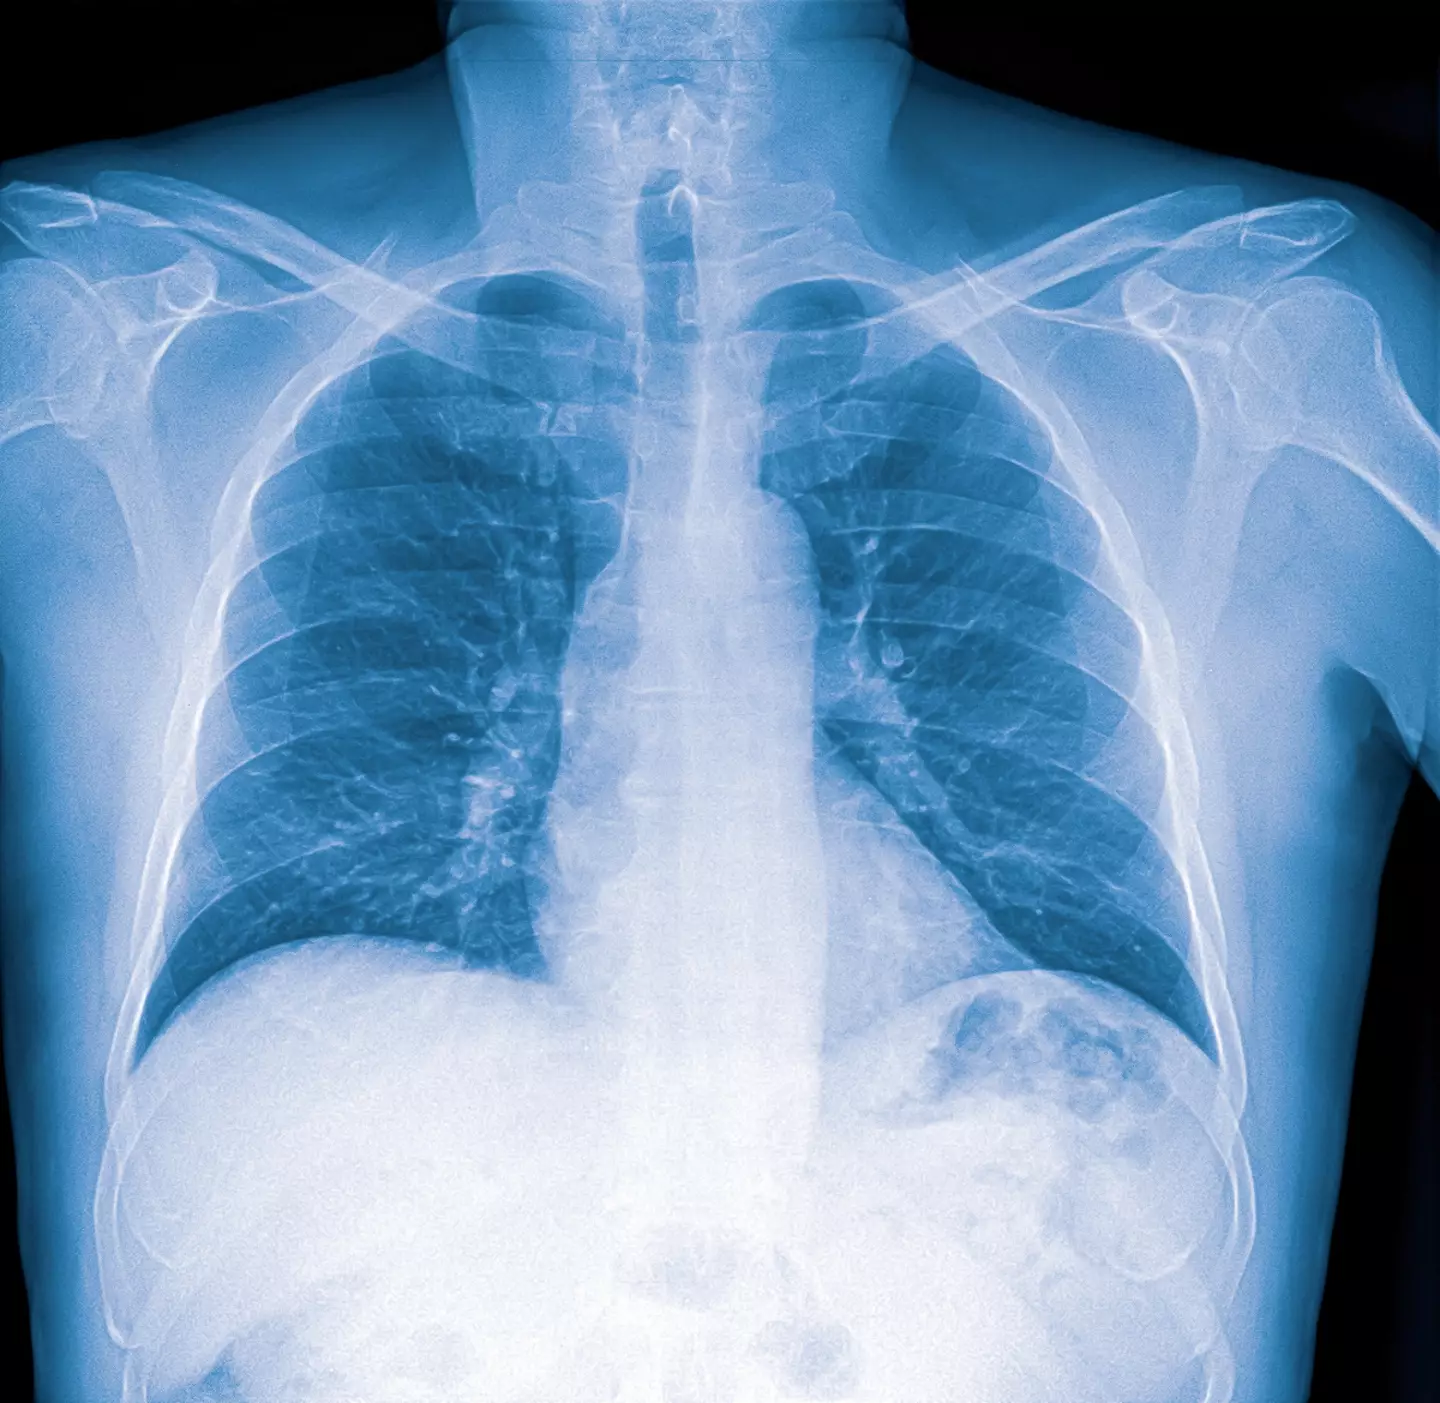

The long-term benefits will start to shine through, as nicotine takes about three days to leave your system, and within a month, your lungs will begin recovering, according to Djordjevic.

"There’s noticeably less shortness of breath and coughing," she highlighted.

The health expert further explained: "After nine months, lung health improves significantly thanks to the renewal of microscopic hair-like structures inside the lungs that help push out mucus and fight infections."